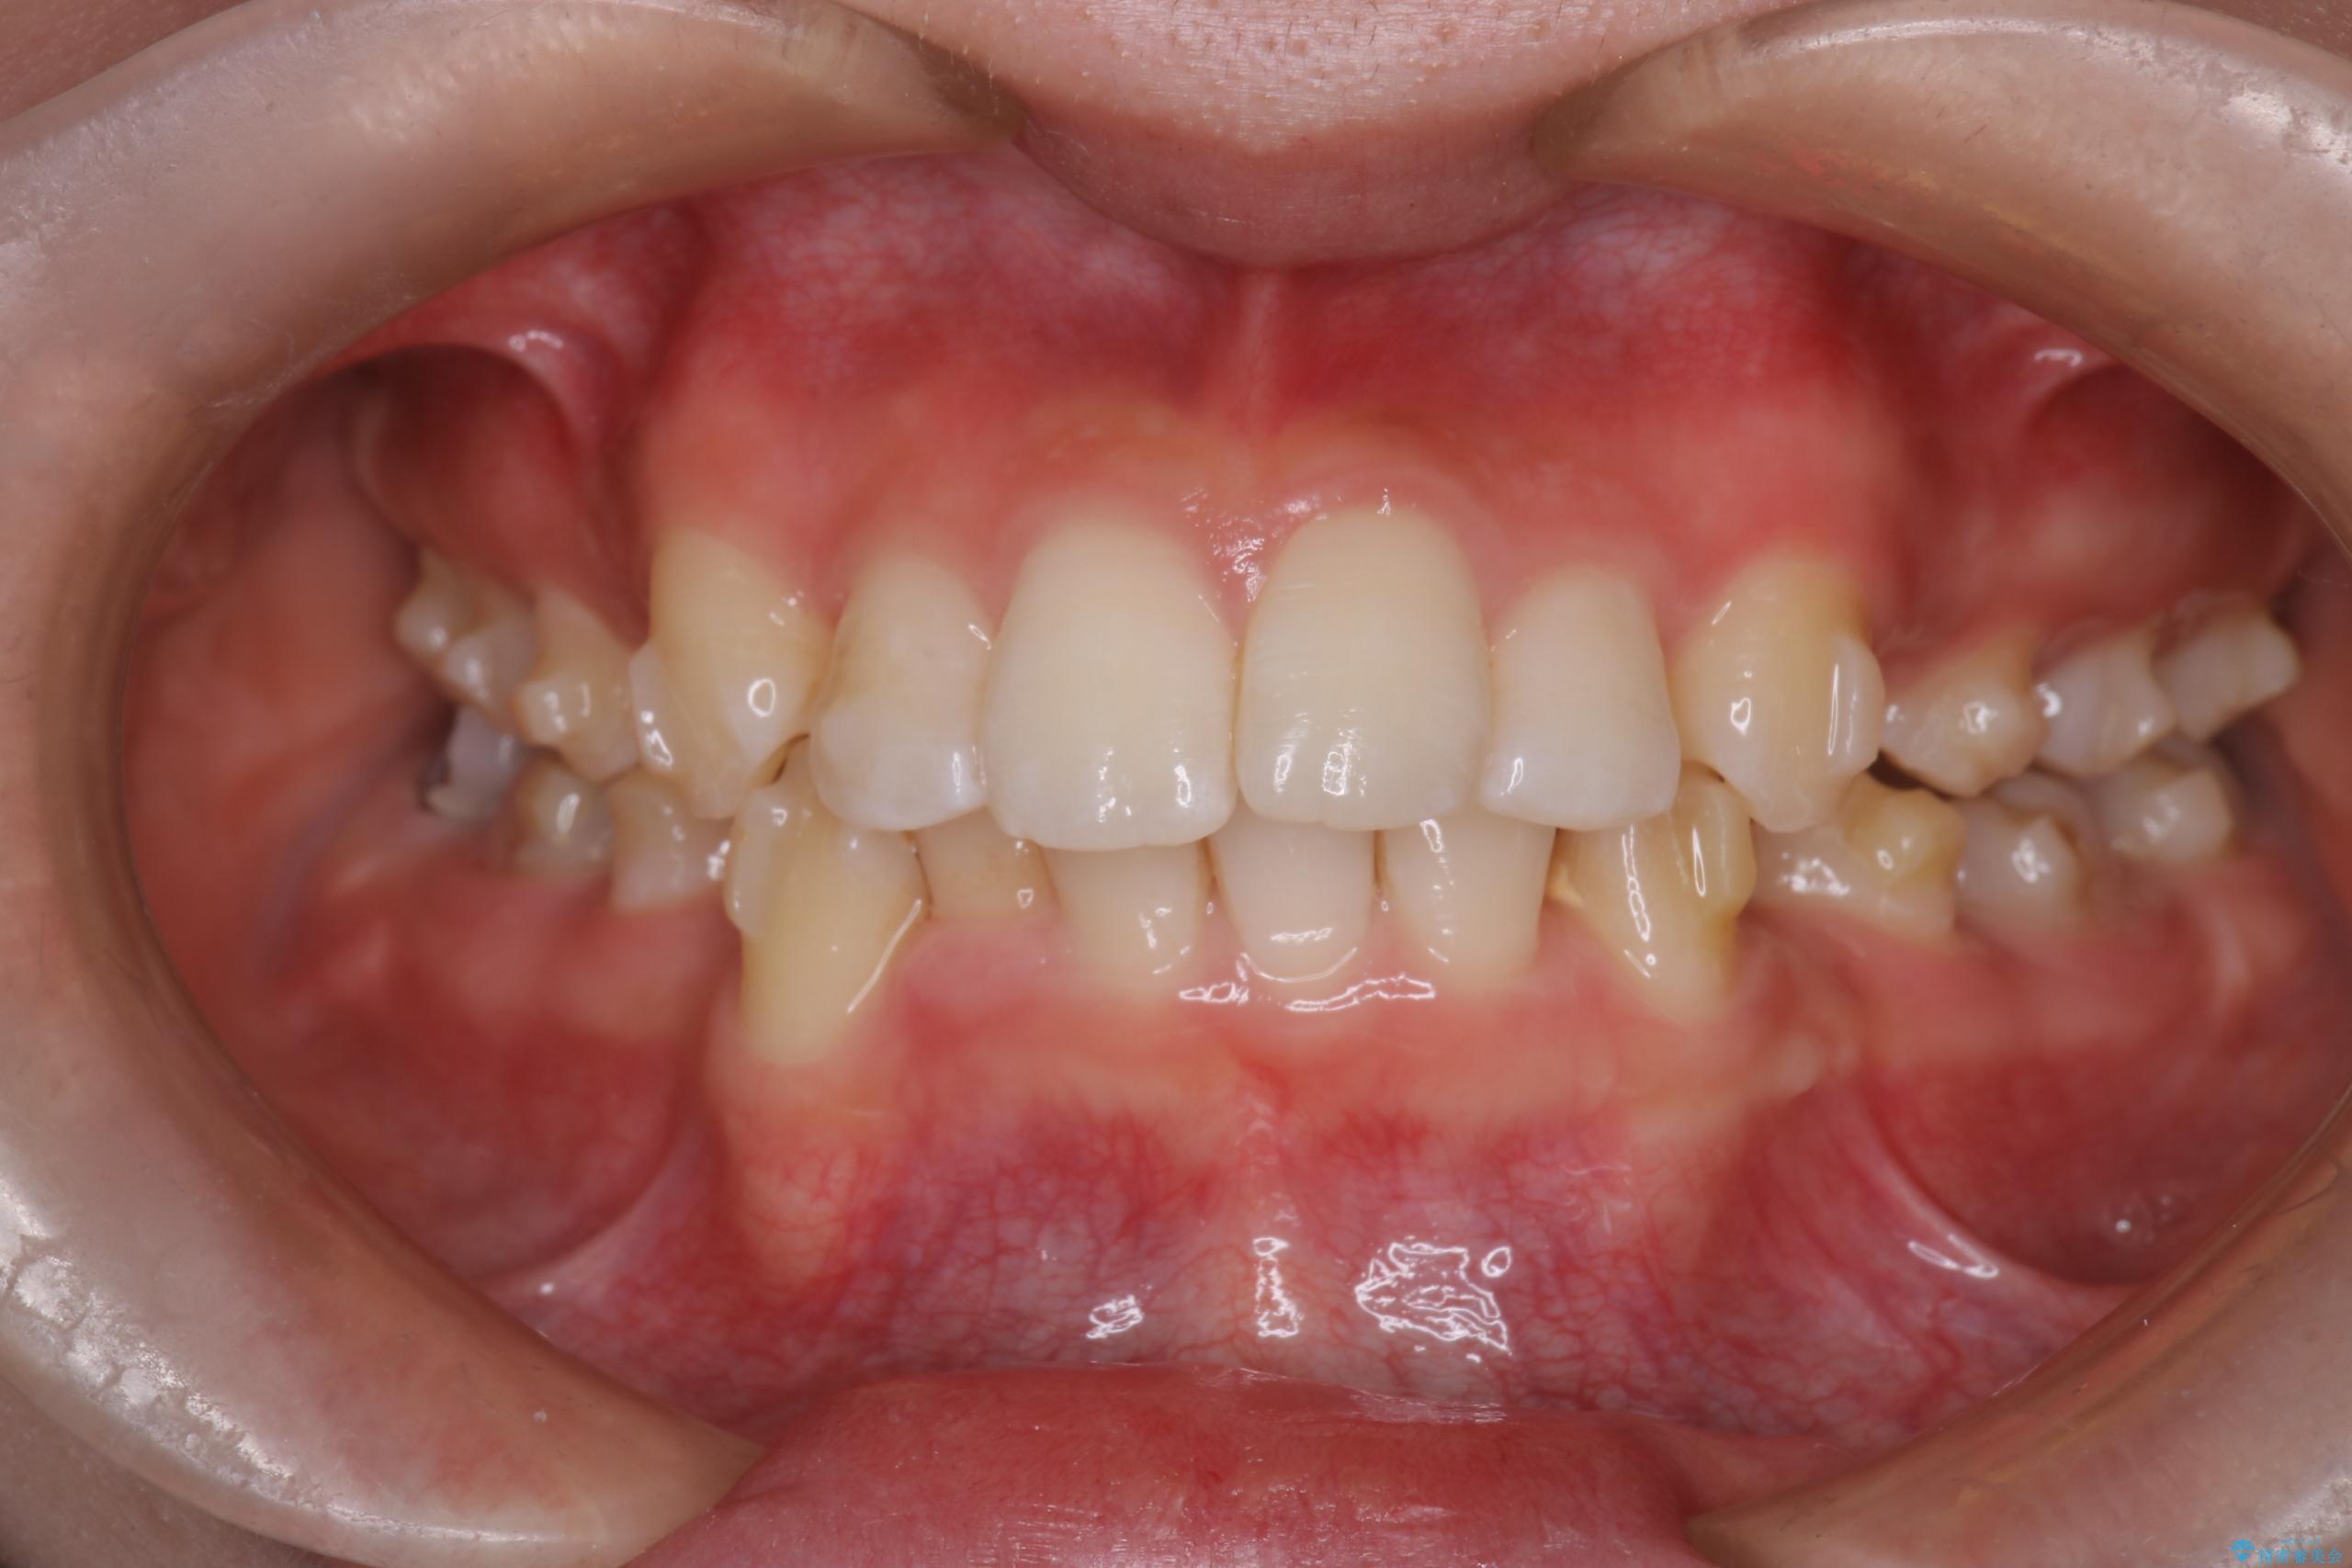

- 前歯から奥歯にかけて歯の重なりが激しい歯のがたつき(重度叢生)を主訴にご来院されました。精密検査の結果、歯が並ぶスペースが大幅に不足しており、歯並びを整え、口元を美しく引っ込めるためには、スペースの確保が必要と診断しました。そこで、上下左右の第一小臼歯(4番目の歯)を計4本抜歯し、そのスペースを利用して歯並び全体を整える抜歯矯正の治療計画を立案。装置には、透明で目立たないインビザラインを採用し、審美性と治療効果の両立を目指しました。

今回の治療では、重度の叢生を改善するため、まず計画通り上下左右4本の小臼歯を抜歯し、歯を並べるための十分なスペースを確保しました。装置には透明で取り外し可能なインビザラインを使用。抜歯によってできたスペースを最大限に活用し、マウスピースを定期的に交換しながら、デコボコを解消しつつ、前歯を効果的に後退させました。

治療の結果、長年の悩みであった重度の歯のがたつきが解消され、口元の突出感も改善。機能的にも安定し、審美的にも美しい、理想的な歯並びを獲得していただけました。